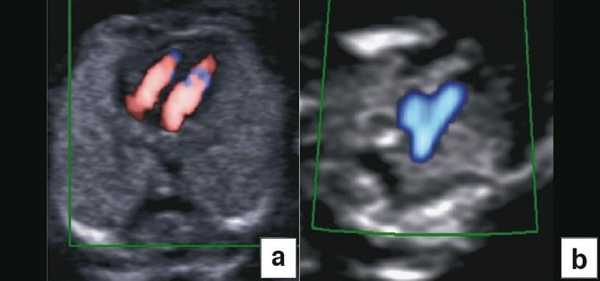

Врожденные пороки сердца

В группах с высоким риском развития врожденных пороков сердца (ВПС) эхокардиографию плода можно проводить на ранних сроках. Обычно исследование выполняет специалист, хорошо знакомый с пренатальной диагностикой ВПС. Высокий риск развития ВПС у плода выявляют не только по данным анамнеза пациентки и семейного анамнеза или воздействия токсических факторов, но и по увеличению ТВП и изменению кровотока в венозном протоке и через трехстворчатый клапан [9]. "Подробную" эхокардиографию плода обычно проводят только в группе высокого риска, а проводить "базовую" эхокардиографию в общей популяции в настоящее время не рекомендовано.

Тем не менее "базовое" УЗИ обычно дополняют исследованием в цветовом энергетическом допплеровском режиме с тщательным анализом для выявления атриовентрикулярного кровотока в четырех камерах сердца (рис. 6a) и в срезе через три сосуда и трахею (рис. 6b). Получив эти срезы, обычно можно успокоить родителей, исключив наличие тяжелых пороков сердца, таких как единственный желудочек, гипоплазия желудочков, полный дефект предсердно-желудочковой перегородки (atrioventricular septal defect - AVSD), атрезия аорты или легочной артерии, а также ряд аномалий расположения артерий.

Рис. 6. Эхокардиография плода на ранних сроках в цветовом энергетическом допплеровском режиме - визуализируются четыре камеры (a) и срез через три сосуда и трахею (b).